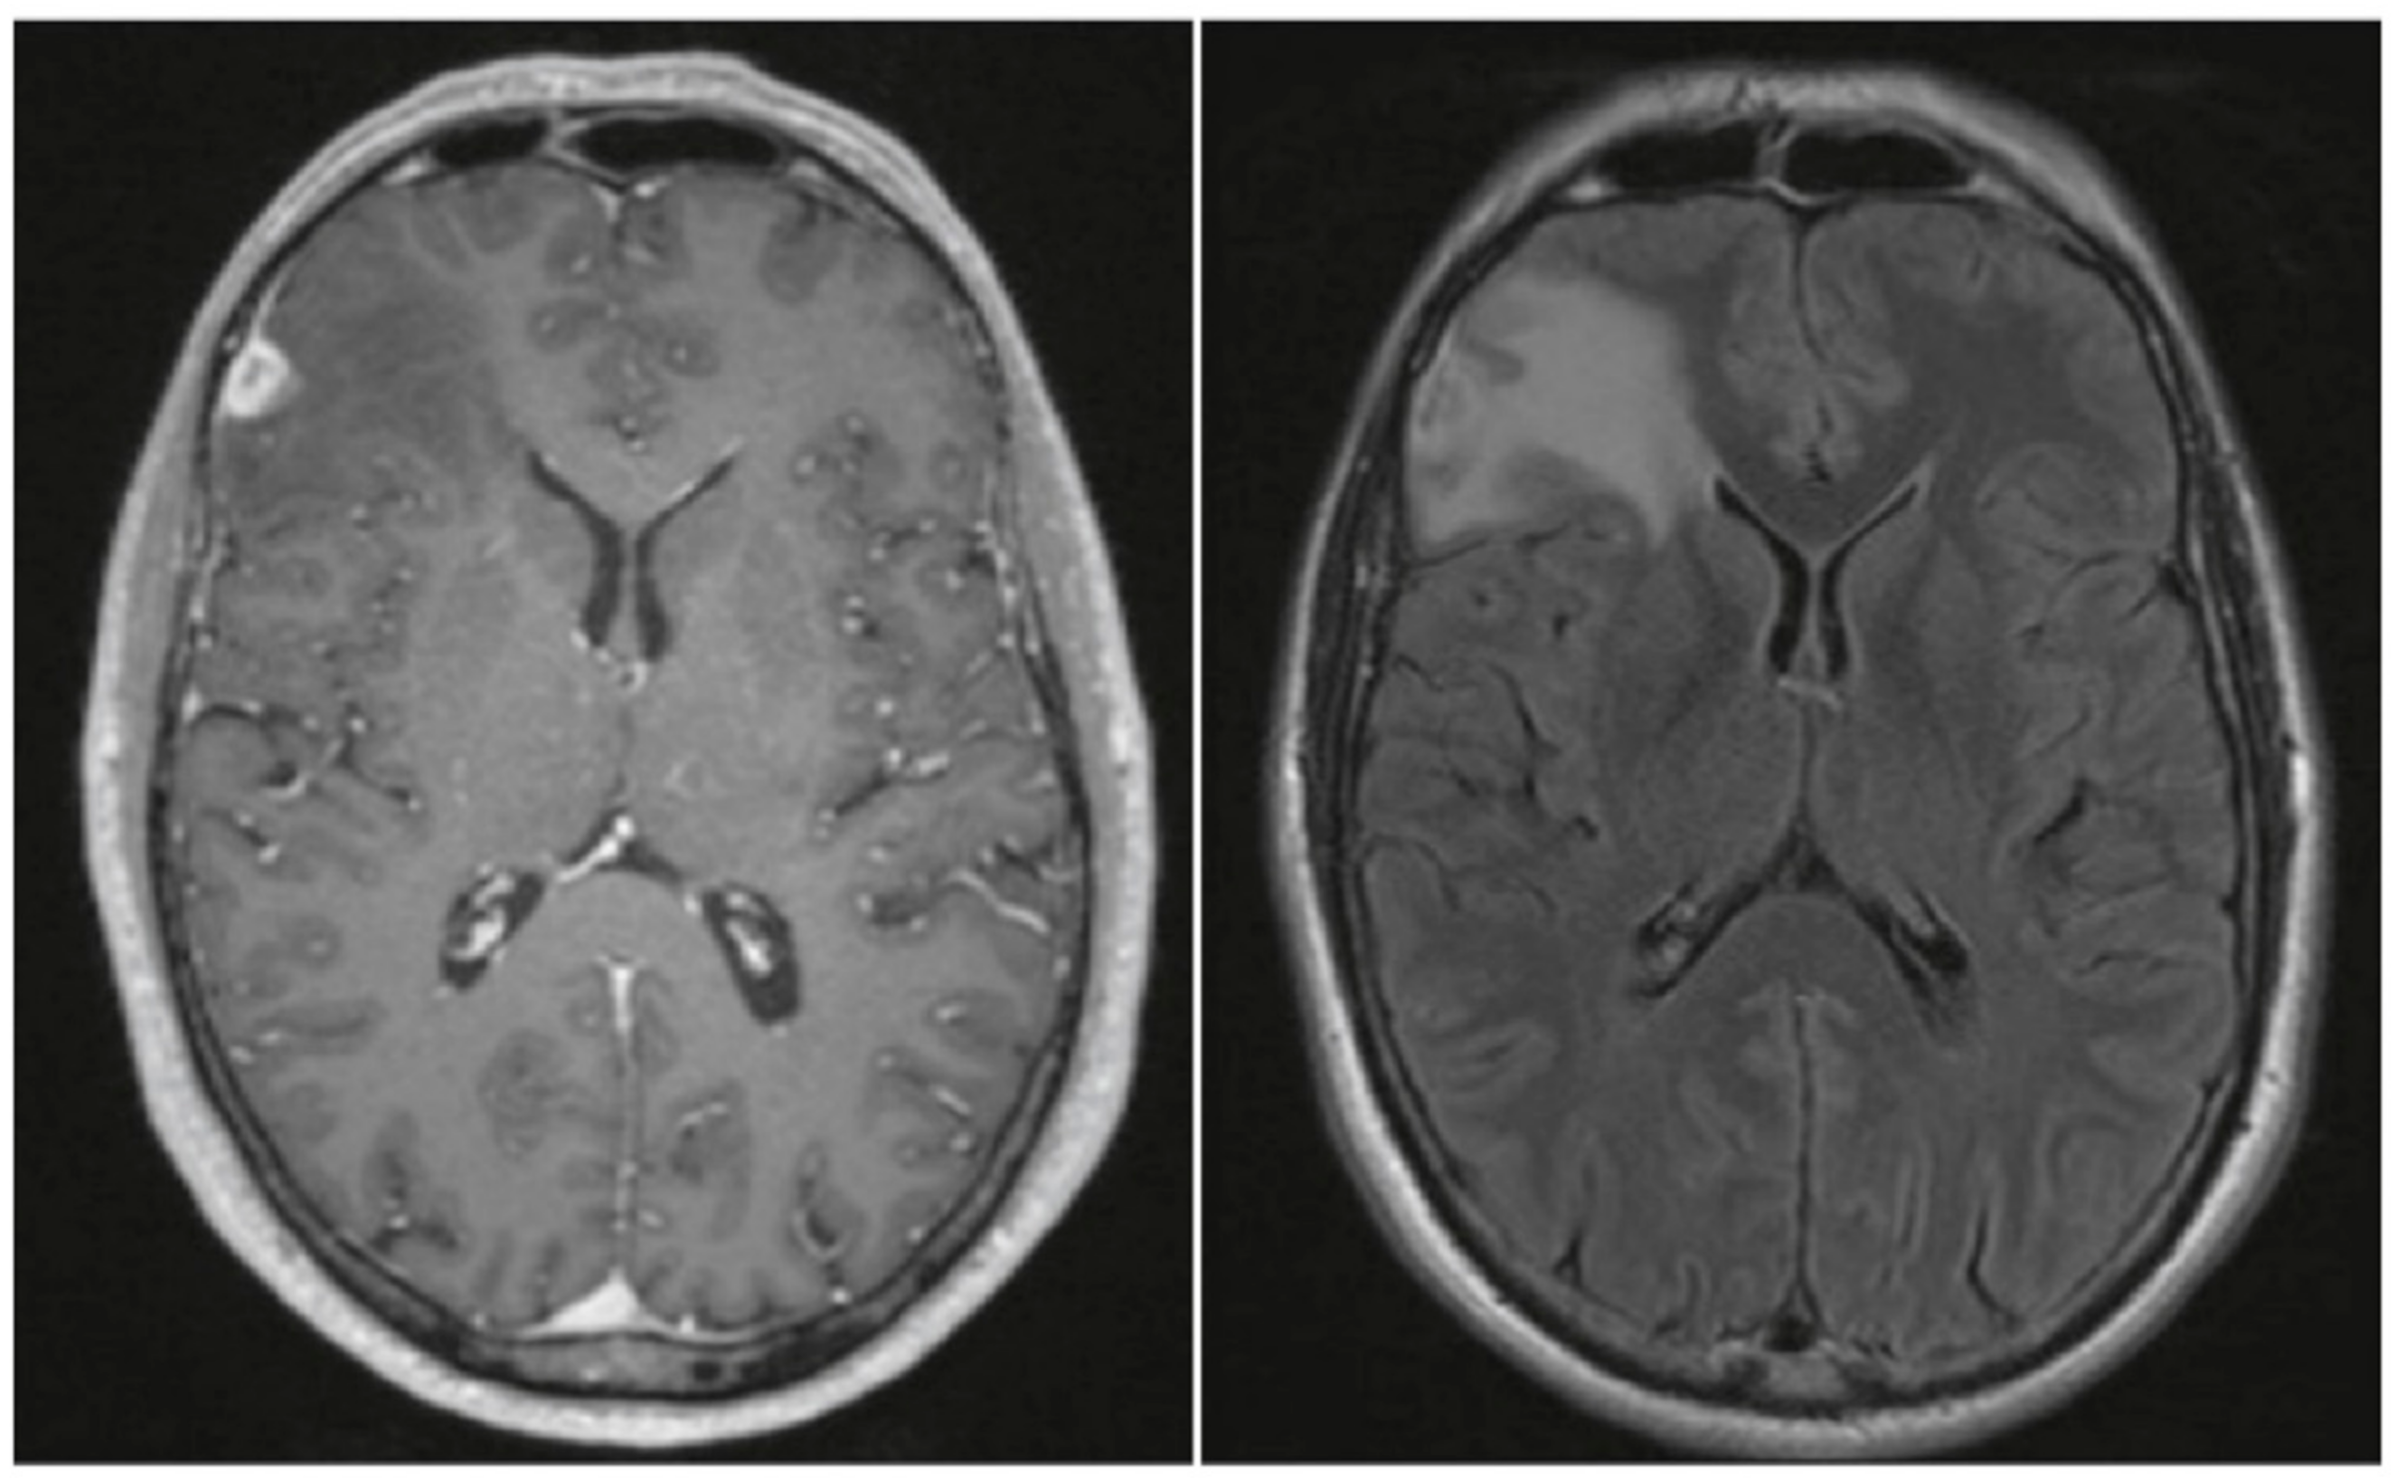

| 22 | Immunohistochemical stains: Toxoplasma spp.- and T. pallidum-negative; staining with antibodies to GFAP, p53, and IDH1-R132H negative. | Contrast-enhancing lesion with perifocal edema, contrast enhancement. | This case | |